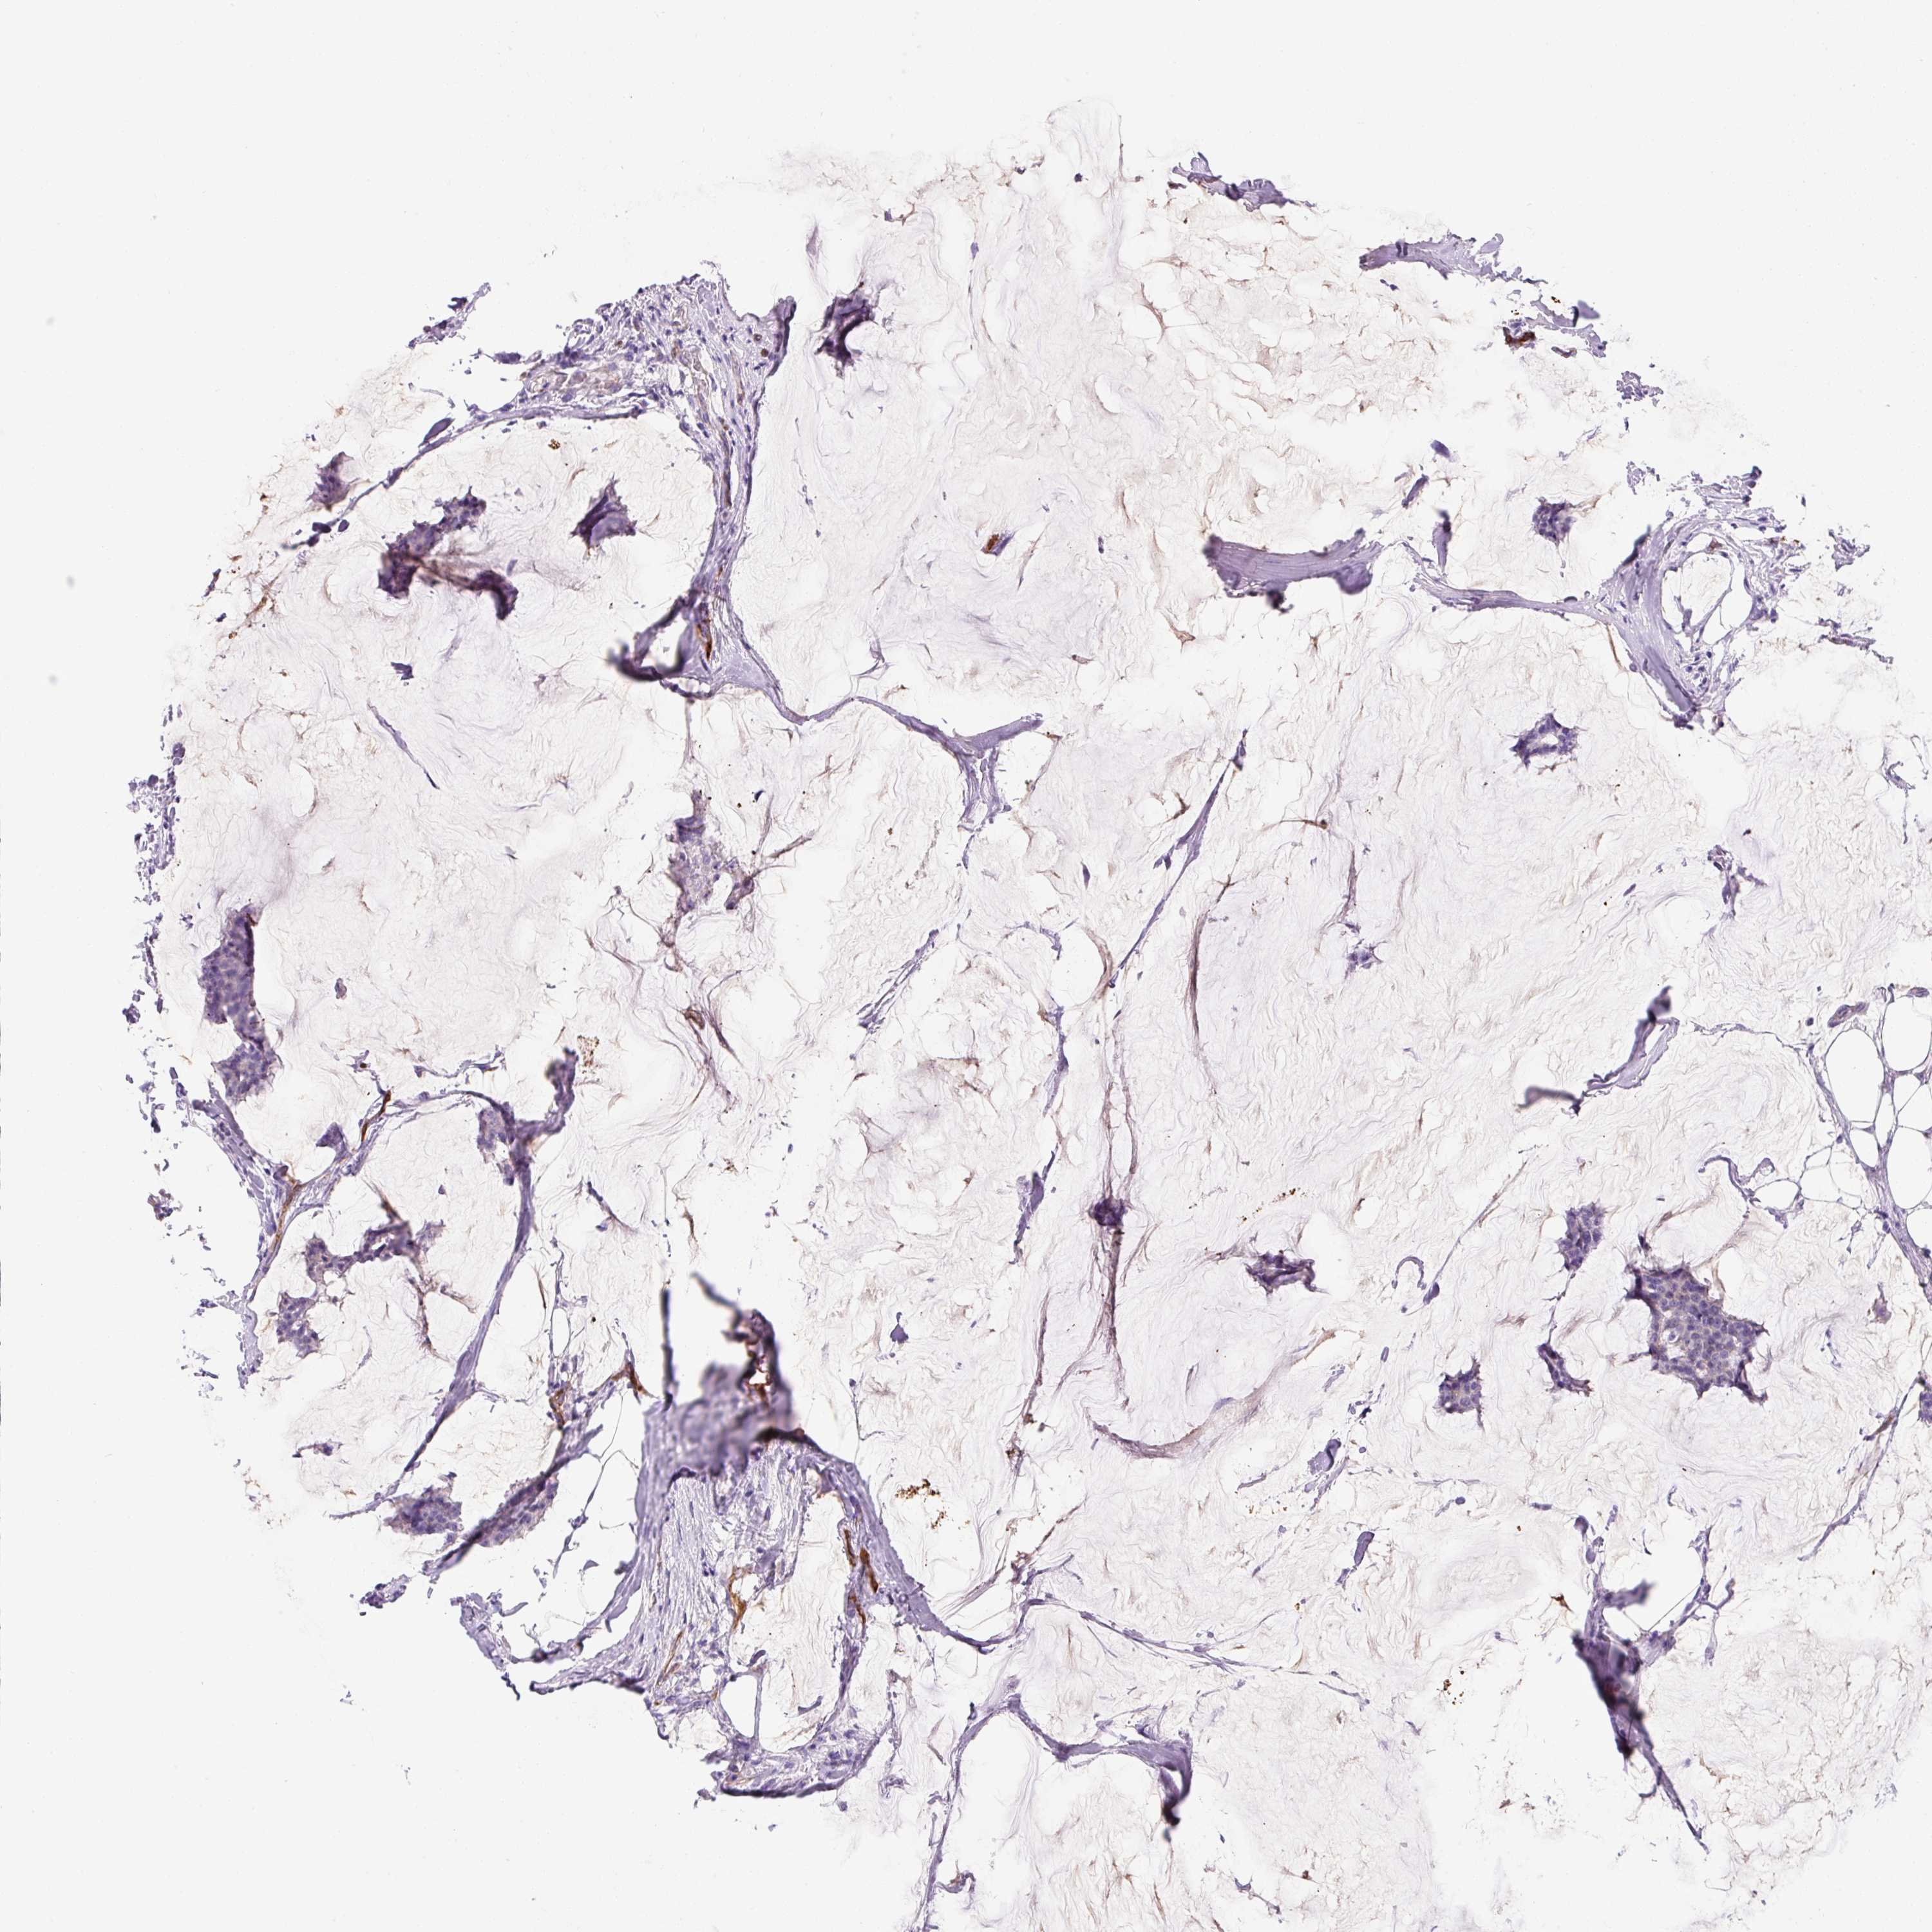

BRCA TCGA BRCA VALIDATION PROTEIN EXPRESSION

ANTIBODIES

AND

VALIDATION